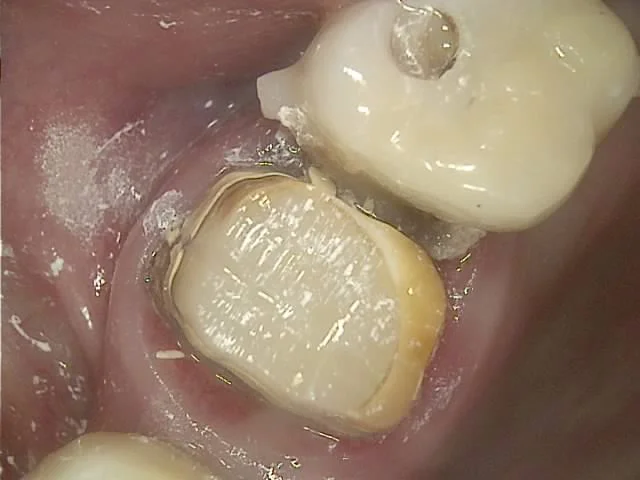

임플란트 음식물 끼임 잇몸 부음 사진

음식물이 고여 있고 주변 잇몸이 부어있는 상태

임플란트와 인접 치아 사이 틈새

임플란트와 바로 앞 치아 사이가 문제

사진을 보면 음식물이 고여 있고 주변 잇몸은 많이 부어있는 양상인데요. 임플란트와 그 바로 앞 치아 사이가 문제입니다.